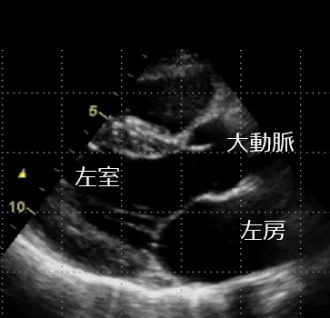

心臓の構造のなかで、左房と左室の間にある膜状の構造を僧帽弁といいます。僧帽弁の働きで左房から左室に送り出された血液は、左室が収縮した際、一方向性に大動脈へ向かい全身に循環します。しかし、僧帽弁に連なる腱が切れたり、左室や左房が過度に大きくなったりすると、僧帽弁がうまく閉じなくなることがあり、逆流が生じます。その量が増えると、息切れ、むくみといった心不全症状や心房細動という不整脈を呈することがあります。このような病状を僧帽弁閉鎖不全症と呼び、高度になると、薬剤治療は功を奏さず、僧帽弁の修復術や人工弁への置き換えが必要となります。

正常の僧帽弁